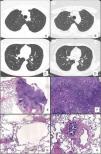

Chest HRCT scans showing diffuse cystic lung disease and a solitary pulmonary nodule (red arrow) in the beginning of follow-up (A and C) and five years later (B and D). (A) Regular and thin-walled pulmonary cysts and a 10mm pure ground-glass nodule in the right upper lobe. (B) CT image at the same level as Fig. 1A after five years of follow-up showing a significant increase in the size of the nodule (13mm) and change in its composition (a solid nodule). (C) Random and multiple thin-walled cysts. (D) Stability of diffuse pulmonary cysts five years later. (E) A low-power view of the tumor with a dense area of scarring. (F) Invasion area with desmoplastic tissue, irregular glands and micropapillae. (G) Constricted airway and peribronchiolar alveolar overdistension. (H) Bronchiole with submucosal fibrosis and focal inflammatory cell infilltrate. (H&E stains, original magnification (A) ×10, (B) ×50, (C) ×40 and (D) ×100).

After 5 years of follow-up, PFTs were stable and there was an increase in the nodule size (13mm), with a solid composition (Fig. 1). There was a mild increase of glycolytic metabolism (SUV 2.6) on the combined positron emission tomography/CT. There was no evidence of lymph node enlargement or extrapulmonary disease. A right upper lobectomy with lymphadenectomy was performed after an adenocarcinoma has been confirmed in the intraoperative frozen section. Histopathological analysis revealed a predominantly acinar invasive adenocarcinoma, with lepidic and micropapillary components, which was classified as Stage IA (T1aN0M0). The lung parenchyma around the tumor revealed a heterogeneous small airway disease characterized by variable narrowing of the small airways, abnormal bronchioles with subepithelial fibrosis and scattered chronic inflammatory cells, associated with peribronchiolar alveolar overdistension, which was consistent with constrictive bronchiolitis (Fig. 1).